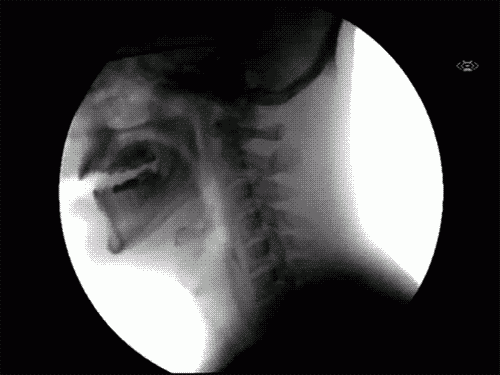

Taky vás vždycky zajímalo, na jakém principu fungují některé každodenní věci? Jak to vypadá, když vám zuby spravují rovnátka? Co se děje v krku, když polykáme sousto? Těchhle 7 gifů vám to názorně předvede.